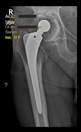

The guiding wire was inserted and controlled with fluoroscopy flashes (Figure 4). The drilling and reaming were carried out in accordance with the recommendations:

Figure 4.

The biocompatible aiming device after insertion of the guiding wire.

The radiological examination allowed us to verify the close bone-to-implant contact and the unchanged position of the implant during follow-up.

In all the cases operated with the above-described targeting procedure, the stems of the cups remained between the cortical bone surfaces without perforation of the linea terminalis, as shown by postoperative radiographs. There were no complicated surgical situations. In 16 cases, the wound healings were uneventful, and the hips were able to bear weight again after postoperative rehabilitation.